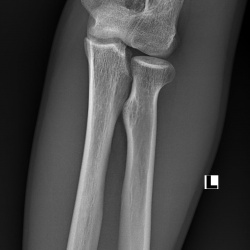

Пациент 35 лет. Состояние после автомобильной аварии; неоднократные операции на плечевой кости.